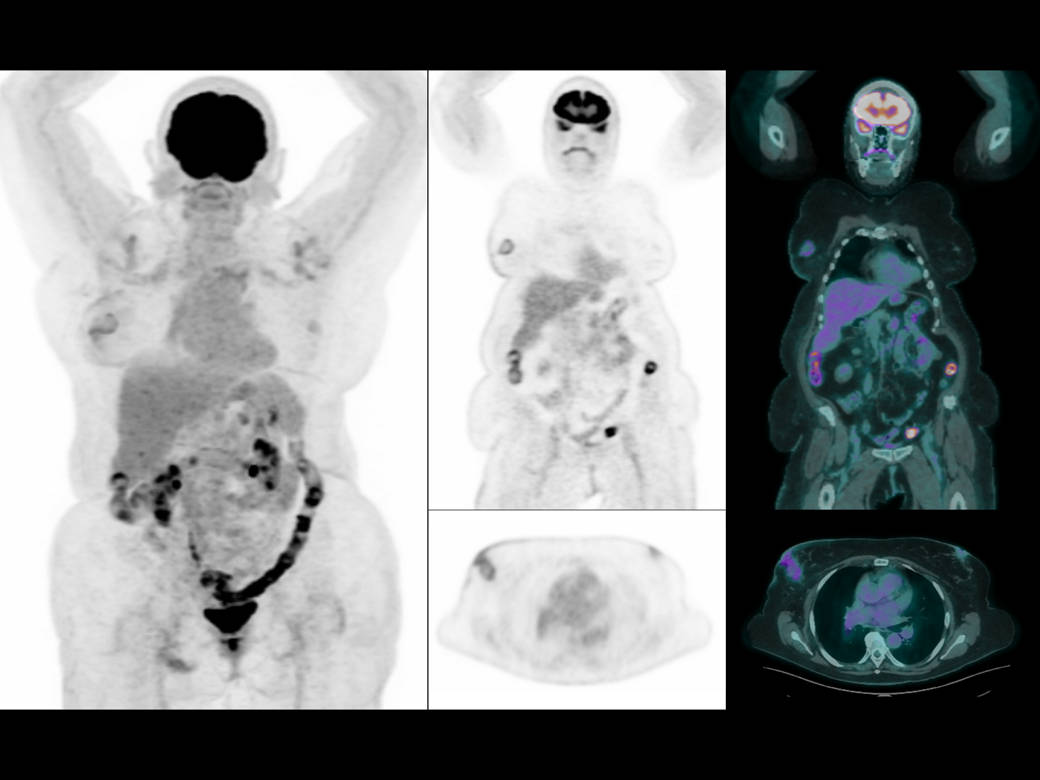

Clarity with a low dose in a large BMI patient*

Clarity with a low dose in a total-body scan*

*Images Courtesy of Pueblo Medical Imaging